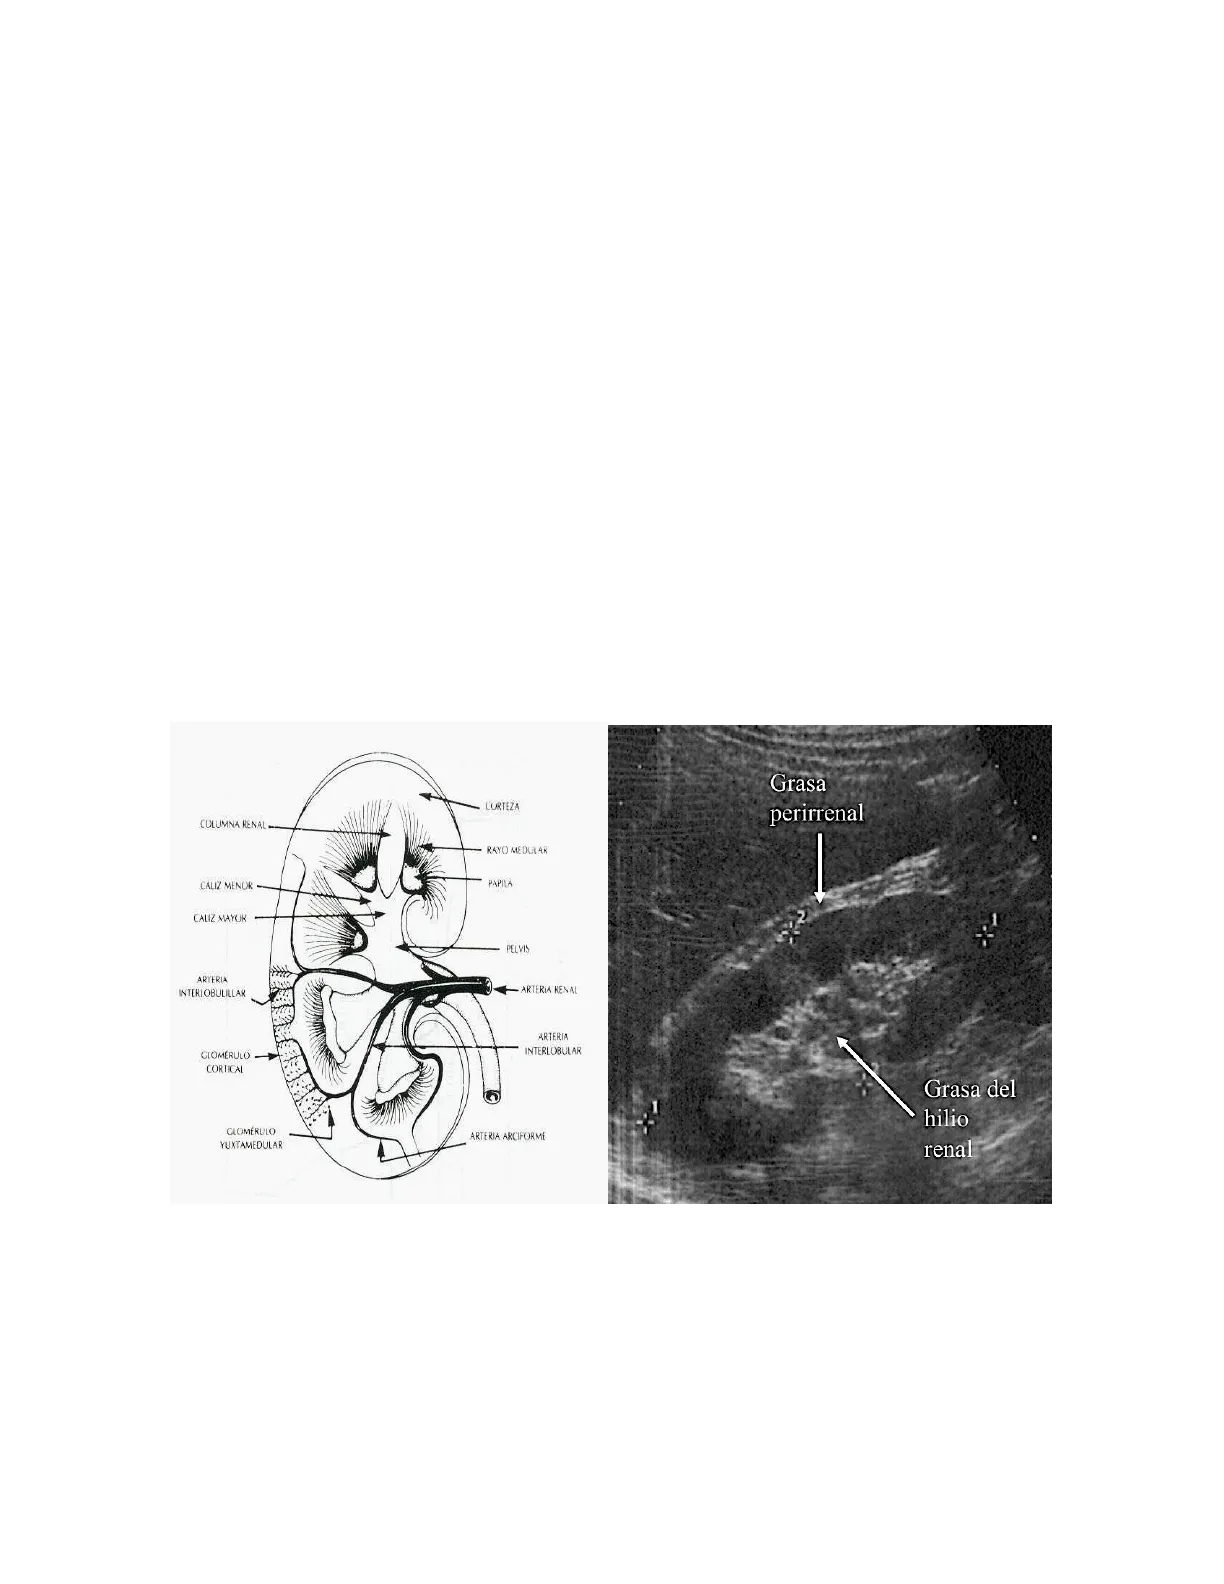

El riñón es un órgano par que se ubica en la región retroperitoneal, entre el nivel de la doceava vertebra torácica y la tercera vertebra lumbar, su aspecto normal semeja un frijol de gran tamaño, el riñón derecho se ubica en posición mas baja al ser desplazado por el hígado, tienen una longitud de 12+/- 2 cmts, amplitud 6 cmts y grosor 3 cmts, su peso en un adulto normal es de 150 a 170 gramos. Por el hilio renal a cada riñón llega una arteria y egresa una vena, la vena renal del lado izquierdo es mas larga que la del lado derecho, aspecto anatómico aprovechado por los cirujanos de trasplante, quienes preferencialmente lo utilizan en las nefrectomías de los donantes renales. Cada riñón esta rodeado de la grasa perirrenal, tejido abundante también en el hilio donde ecográficamente genera imágenes características por su ecogenicidad (ecodensas). En la parte superior de los riñones se encuentran las glándulas suprarrenales (Figura 1 y 2).

CORTEZA COLUMNA RENAL RAYO MEDULAR CALIZ MENOR ΡΑΡΙΤΑ CALIZ MAYOR PELVIS ARTERIA INTERLOBULILLAR ARTERIA RENAL ARTERIA INTERLOBULAR GLOMERULO - CORTICAL ARTERIA ARCIFORME GLOMÉRULO YUXTAMEDULAR

Figura 1. Estructura renal normal

Grasa perirrenal Grasa del hilio renal

Figura 2. Aspecto ecográfico renal